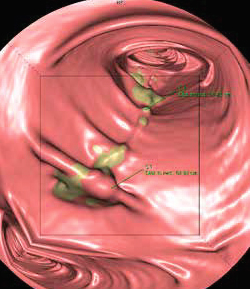

Gastro-abdominal Imaging

Exams we offer include : Colon-Polyp Evaluation, Pre-& Post-Surgical Assessment, Abdominal Cancer, Appendicitis and Vascular Evaluation

CT VIRTUAL COLONOSCOPY

DRCTC is proud to have a mobile CT scanner. This system boasts a wide variety of revolutionary advancements, including being the only Open Gantry Design CT in the marketplace. The system produces the fastest total body imaging time of any CT currently available and the multi-slice CT, allows for highly accurate and precise anatomical mapping.